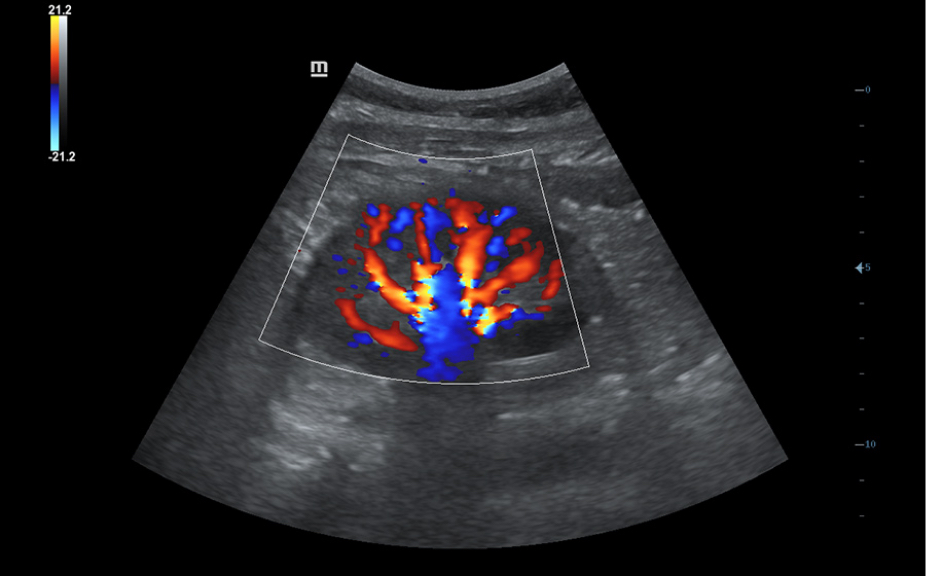

- UWN (Ultra-Wideband Non-linear) Contrast Imaging, Mindray’s unique contrast imaging technology, utilizing contrast agent characters with both 2nd harmonic and non-linear fundamental signals to get improved S/N ratio for better diagnostic details and longer contrast agent duration for better observation.

| Colored | Color Flow Mode, PowerFlow |

| Doppler | CW Color Doppler, PW Color Doppler |